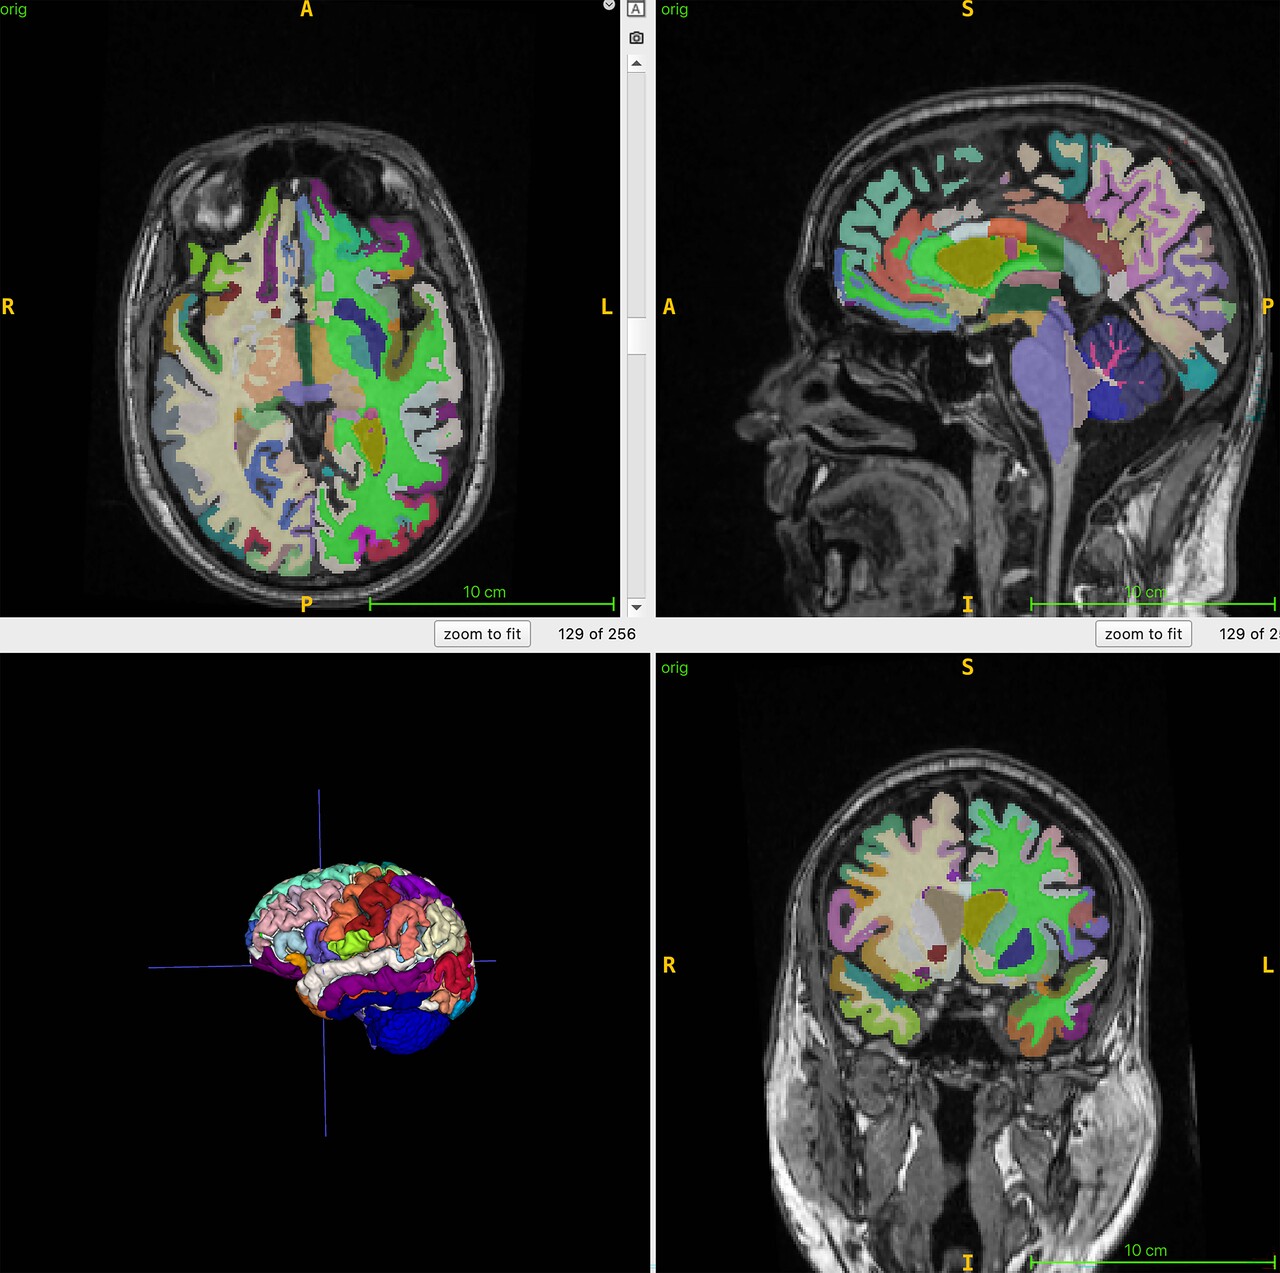

연구팀은 이 연구에서 뇌의 구조적 MRI 영상의 부위별 부피를 기반으로 추정한 뇌 나이와 전신 MRI로 측정한 총근육량과 내장지방, 피하지방 사이의 연관성을 인공지능 알고리즘으로 분석했다.

이들은 4개 지역 거주자 1천164명(평균 나이 55.17세)을 대상으로 전신 MRI를 촬영하고 이를 지방과 체액, 근육 등이 다른 색으로 보이게 하는 기법과 결합해 총근육량과 내장지방 피하지방, 뇌 나이를 정량화했다.